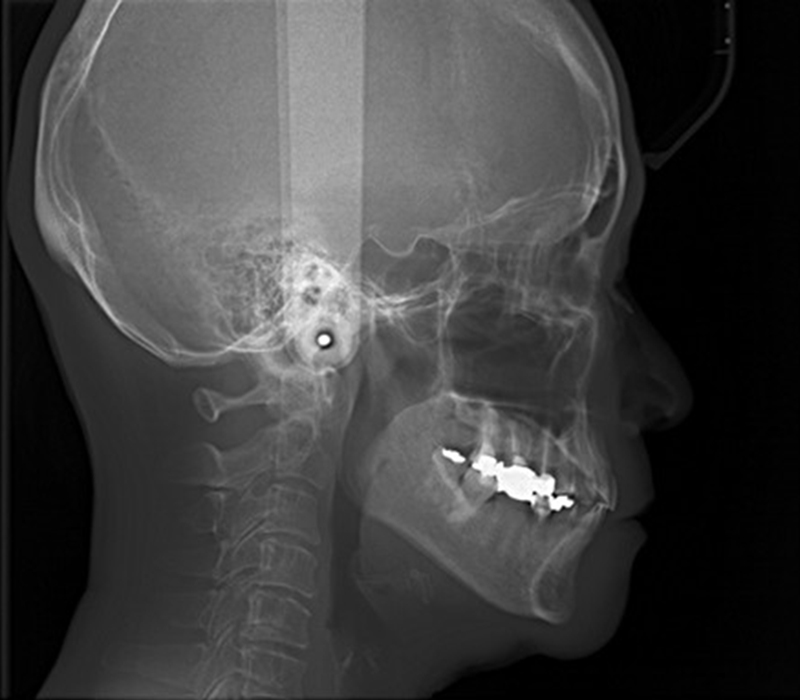

セファロX線写真撮影

歯並びだけでなく顎の骨格や顔全体のバランスを診断

従来の平面的なレントゲンでは見えなかった、隠れた病変や複雑な構造まで正確に把握できるのが、当院が導入している歯科用CTです。

適切な治療には、的確な診断が前提となります。どれほど優れた治療技術があっても、診断が間違っていれば正しい治療はできません。むしろ、誤った診断が原因で不要な治療を行ったり、治療後に合併症や後遺症を引き起こすリスクも伴います。

むし歯や歯周病、親知らず、根管治療、矯正治療、インプラント治療など、さまざまな歯科治療の診断・精度向上のために用いられるのがこの歯科用CTスキャンです。